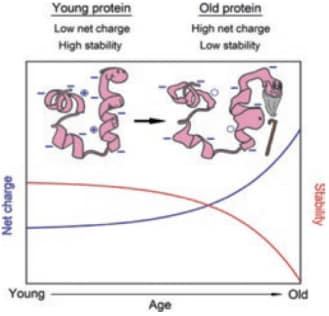

IF Primjena novih nanostrukturiranih materijala u medicinskoj dijagnostici što uključuje istraživanje otpornosti proteina na biološko starenje in vitro i in vivo

Oksidacija proteina jedan je od najboljih markera starenja i upalnih procesa. Metalni nanoklasteri: Novi detektori karbonilacije proteina 2D-oxyDIGE gel proteina ljudske plazme.

Glutation reduktaza, modelni protein koji koristimo za razvoj detekcije proteinske karbonilacije uz pomoć metalnih nanoklastera.

Razvoj i primjena metalnih nanoklastera za detekciju i kvantifikaciju proteinske karbonilacije in vitro i in vivo Suradnja s prof. Vlastom Bonačić-Koutecký i dr. Rodolphe Antoine (Université Claude Bernard Lyon 1, CNRS, Lyon, France)

Karbonilacija proteina može se detektirati i mjeriti pomoću 2D-oxyDIGE metode koja koristi specifičnu fluorescentnu probu vezanu na hidrazid koji reagira s karbonilnom skupinom.

Kao model koristi se protein SOD1 koji je vezan uz pojavu teške neurodegenerativne bolesti amiotrofične lateralne skleroze (ALS). Odabrani su mutanti SOD1 za koje se pretpostavlja da će imati veću osjetljivost na karbonilaciju i stvaranje agregata.

Kako bi se poboljšala specifičnost i osjetljivost tehnike, razvijaju se nanoklasteri koji zamjenjuju te ci-hidrazidne boje.